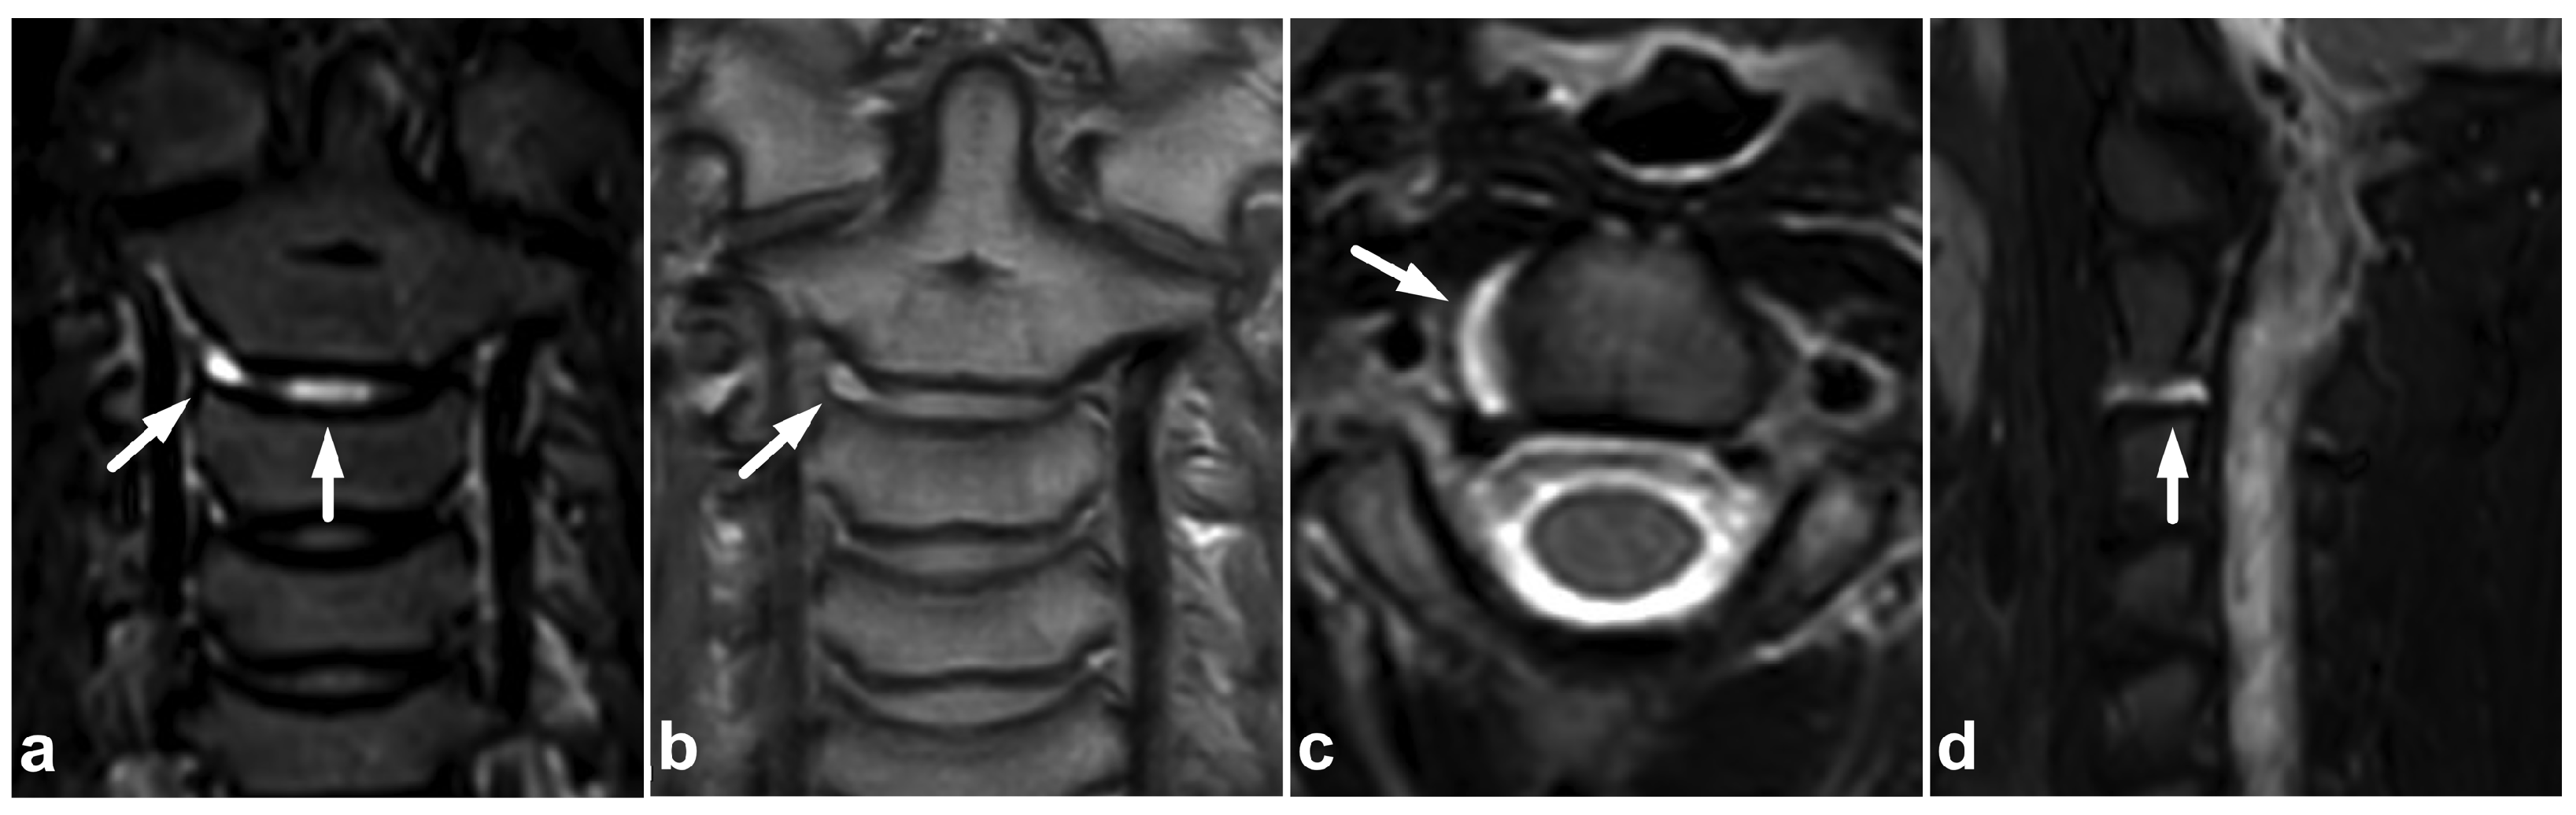

4.1. Occipitocervical and Atlantoaxial Ligaments